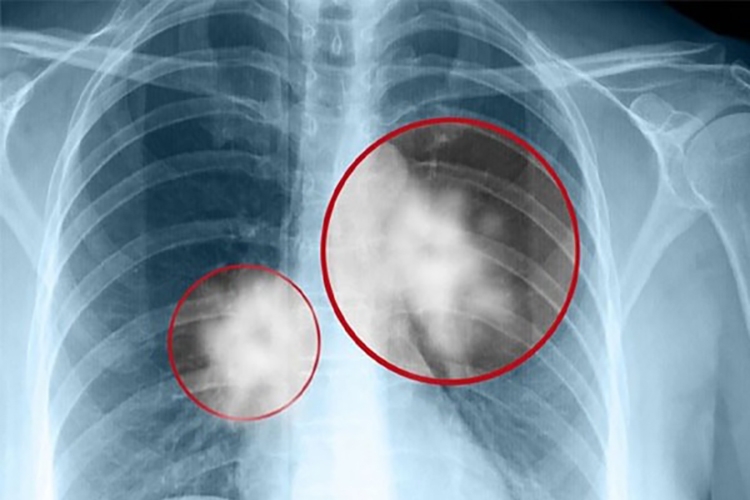

Tác hại lớn nhất của Amiang là gây ra các căn bệnh nguy hiểm như: bụi phổi-Amiang, ung thư phổi, ung thư thực quản, ung thư buồng trứng, ung thư trung biểu mô ác tính màng phổi, tràn dịch và dày màng phổi. Tuy nhiên, ảnh hưởng này không xuất hiện khi đang tiếp xúc với Amiang mà phải đến 20 - 30 năm sau, nghĩa là khi người lao động đã nghỉ hưu.

Theo ước tính, Amiang là chất gây ung thư nghề nghiệp gây ra 1/2 số ca tử vong do ung thư nghề nghiệp trên thế giới. Amiang là nguyên nhân của 80% số trường hợp bị ung thư trung biểu mô ác tính ở người. Lượng người chết do ung thư trung biểu mô ác tính thực tế đang ngày càng gia tăng ở các nước phát triển do đã sử dụng nhiều Amiang trong quá khứ.